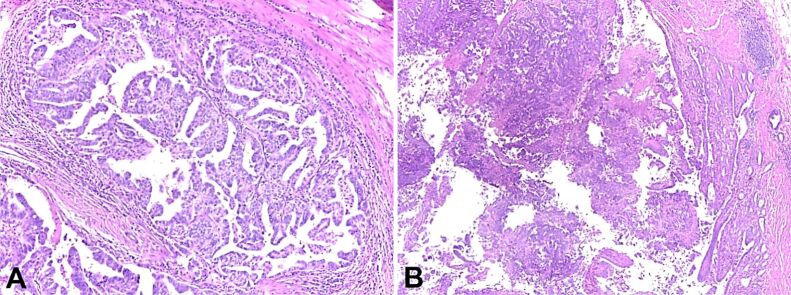

回肠腺癌(ADK)是一种罕见的癌症,具有显著的诊断和治疗困难。本文通过对已有病例文献的分析,探讨幽门腺化生(PGM)与回肠ADK发病的关系。PGM的定义是肠上皮细胞向胃型粘膜的非典型转化,已被认为是几种胃肠道恶性肿瘤谱系中可能的前体病变。我们打算通过对记录病例的详尽检查,阐明临床特征、组织学结果和与源于PGM的回肠ADK相关的结果。我们的研究结果表明,早期识别化生改变可能对改善预后和告知治疗选择至关重要。这项研究强调需要进一步的研究来阐明驱动这种转变的机制,并提高临床实践中的诊断精度。

Adenocarcinoma (ADK) of the ileum is an infrequent cancer that poses significant diagnostic and treatment difficulties. This article analyses the existing case literature to investigate the correlation between pyloric gland metaplasia (PGM) and the onset of ileal ADK. PGM, defined by the atypical transformation of intestinal epithelial cells into gastric-type mucosa, has been recognized as a possible precursor lesion in the spectrum of several gastrointestinal malignancies. We intend to clarify the clinical characteristics, histological results, and outcomes linked to ileal ADK originating from PGM through an exhaustive examination of recorded cases. Our findings indicate that early identification of metaplastic alterations may be essential for enhancing prognosis and informing therapeutic choices. This study emphasizes the need for additional research to elucidate the mechanisms driving this transition and to improve diagnostic precision in clinical practice.